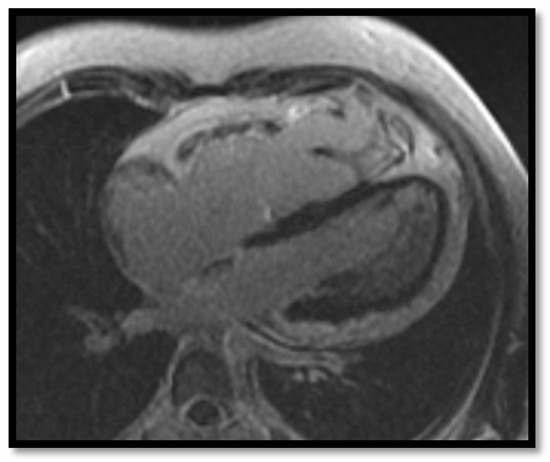

- RV dilation is also a key element for the diagnosis of ARVC. It can be segmental or global. Segmental expansion can affect only the RVOT or parts of the RV such as the basal free wall or the middle third of the free wall. It is a diagnostic criterion with high sensitivity and specificity for ARVC (Figure 3). Only the global dilation of RV is considered a diagnostic criterion for ARVC because segmental dilatation is rather difficult to interpret [12,45].